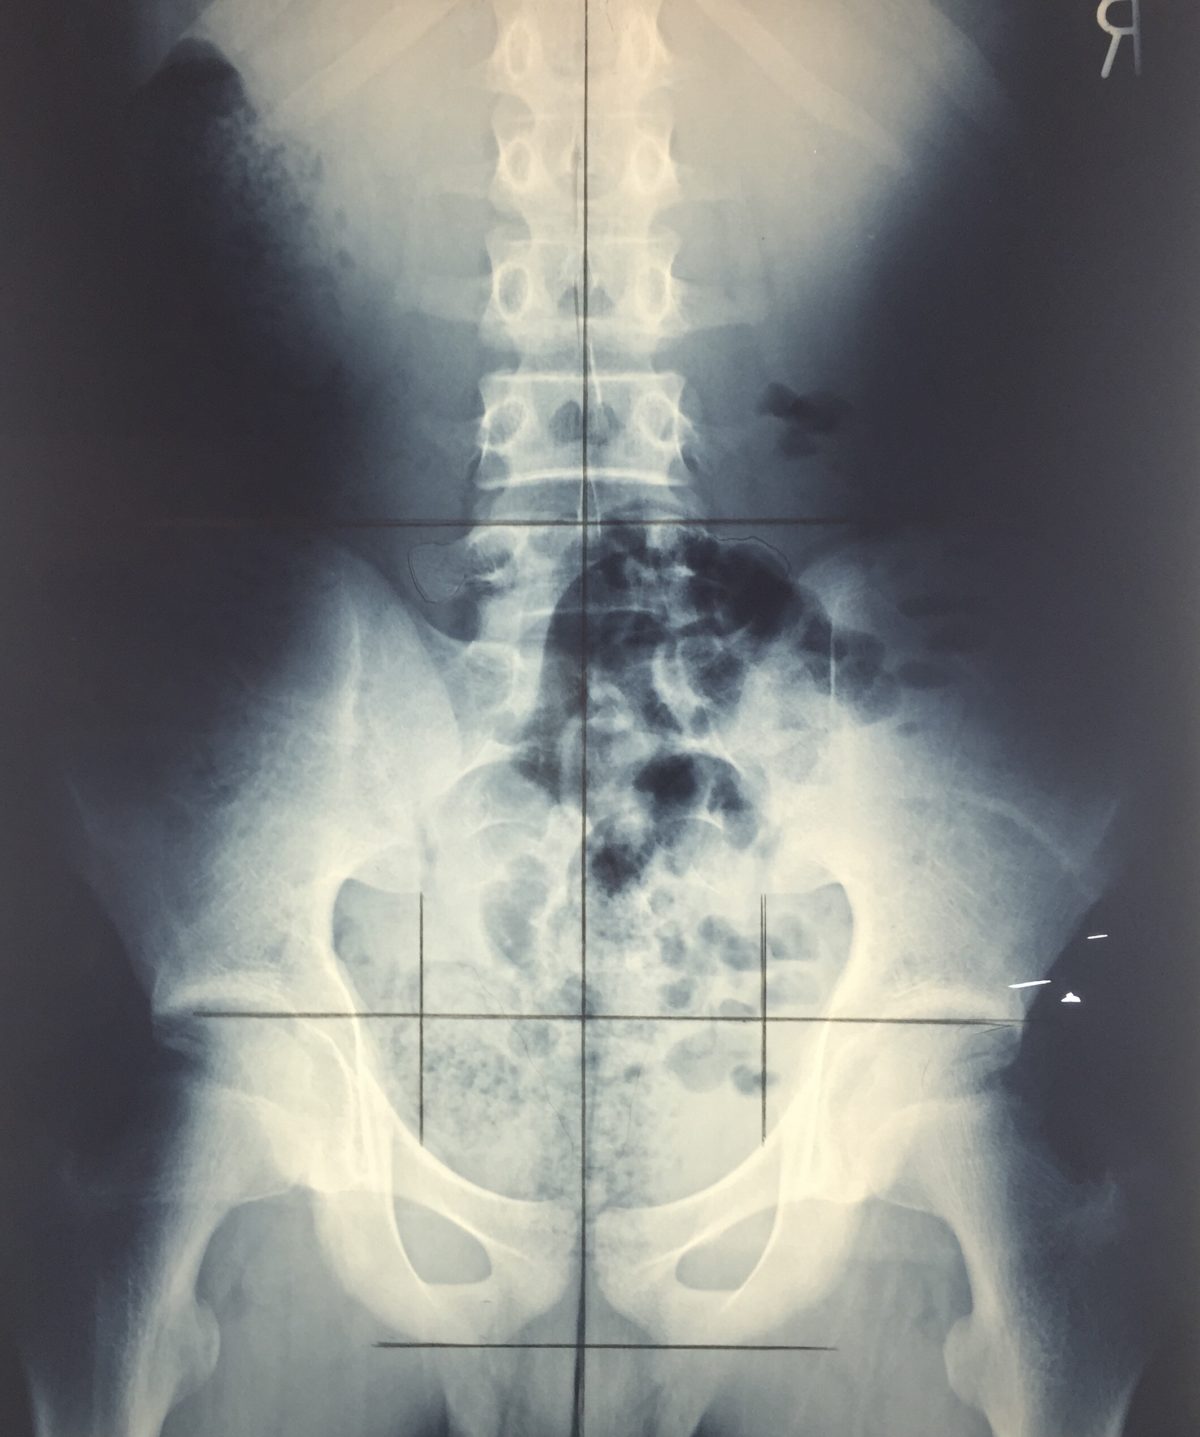

詳細な画像分析

提携医療機関にて、骨盤・腰椎・頚椎(首)のレントゲンを撮影いただき、その画像を詳しく分析します。目視や触診だけでは分からない内部の状態を把握します。

骨盤の状態は、レントゲンなどの体の内部を詳しく見ないと、完全には把握できないのです。